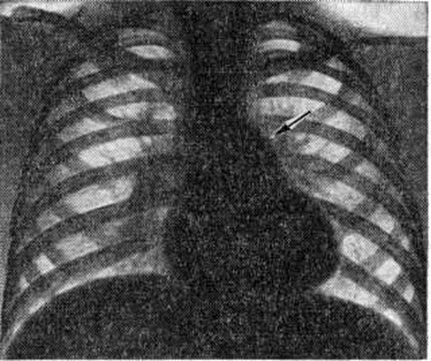

Диагноз. При аортальном стенозе данные векторкардиографии (смотри полный свод знаний) отражают подъём левожелудочкового давления лучше, чем ЭКГ. Только заметное повышение давления (градиент давления на уровне сужения более 60 миллиметров ртутного столба) приводит к появлению на ЭКГ признаков гипертрофии левого желудочка. У новорождённых на ЭКГ могут быть лишь признаки гипертрофии правого желудочка. Характерные клинические, симптомы в сочетании с признаками гипертрофии левого желудочка на ЭКГ указывают на выраженный аортальный стеноз (рисунок 3). При рентгенологическое исследовании у детей тень сердца нормальных размеров или с признаками гипертрофии левого желудочка. При высоком конечно-диастолическом давлении в левом желудочке и левом предсердии отмечаются застойные явления в прикорневых отделах лёгких. Может быть расширена восходящая часть аорты (постстенотическая дилатация). У детей с выраженным стенозом рентгенологически определяется аортальная конфигурация сердца (рисунок 4) и усиленный легочно-сосудистый рисунок. При ретроградной катетеризации сердца катетер проводят через место сужения в полость левого желудочка, измеряют градиент давления, выявляют место сужения и возможные сопутствующие пороки. У новорождённых и грудных детей катетеризация сердца может быть заменена эхокардиографическим исследованием (смотри полный свод знаний: Эхокардиография). У больных с асимметричной перегородочной гипертрофией во время систолы происходит смыкание передней створки левого предсердножелудочкового (митрального) клапана с гипертрофированным миокардом. Сужение может сопровождаться большим градиентом давления. При нагрузках, приёме сердечных гликозидов или инотропных средств и нитроглицерина градиент давления возрастает, но снижается при использовании р-адреноблокаторов (анаприлина, обзидана, индерала). Во время систолы, следующей после экстрасистолы, артериальное давление уменьшается, в то время как при других видах аортальногостеноза оно возрастает. При массивной мышечной гипертрофии возникает обструкция выходного отдела левого желудочка, нарушается функция митрального клапана. Признаки заболевания аналогичны таковым при других видах аортального стеноза, однако на ЭКГ всегда регистрируют выраженную гипертрофию левого желудочка, удлинение интервала Q — Г, изменения S — Г, зубцов Т и Q. Диагноз может быть установлен достаточно точно с помощью эхокардиографии. Во время катетеризации сердца на киноангиокардиограмме (смотри полный свод знаний: Ангиокардиография) в боковой проекции видно сужение полости левого желудочка в его выходной части. Детей с сердечной недостаточностью оперируют по жизненным показаниям. Так называемый плановые операции при аортальном стенозе выполняют, если в покое градиент давления на уровне сужения выше 60 миллиметров ртутного столба. Аортальную вальвулотомию производят либо по закрытой методике (через верхушку сердца в аорту последовательно проводят вальвулотом и дилататор), либо на «открытом» сердце в условиях умеренной гипотермии (общей или краниоцеребральной) при пережатых полых венах. Доступ — через стенку аорты. В течение 3—5 минут рассекают клапан по комиссурам. Безопаснее устранять порок в условиях искусственного кровообращения. Наибольшие трудности возникают при коррекции надклапанного сужения с гипоплазией аорты, что требует вшивания заплаты в стенку аорты, иногда с протезированием клапанов сердца (смотри полный свод знаний), и асимметричной гипертрофии миокарда. Иссечение мышечных масс может быть выполнено из аортального доступа, который иногда приходится дополнять рассечением стенки левого желудочка. Существуют методики, предусматривающие иссечение миокарда со стороны правого желудочка. К более радикальным операциям относится иссечение миокарда через левое предсердно-желудочковое отверстие с последующим протезированием митрального клапана. Ок. 10% неоперированных детей раннего возраста имеют явные признаки левожелудочковой недостаточности. В течение первого года жизни (особенно первого месяца) большая их часть погибает. У выживших со средней степенью сужения клинические, признаки Пороки сердца врождённые с возрастом нарастают. Страдающие тяжёлой формой стеноза в 1—7% случаев умирают внезапно. В 20% случаев при стенозе развивается регургитация. При асимметричной гипертрофии перегородки сердца продолжительность жизни ограничена 40—50 годами. Результаты оперативного лечения во многом определяются исходной степенью тяжести стеноза, его морфологией, состоянием миокарда левого желудочка, радикальностью оперативного вмешательства и отсутствием послеоперационной недостаточности клапана. Операционная летальность не превышает 10%. Через 10 лет около 25% оперированных нуждается в повторном вмешательстве для ликвидации рестеноза или регургитации. Во время повторных операций, как правило, производят протезирование клапана. У остальных отдалённые результаты хорошие и удовлетворительные: большая часть из них может считаться практически здоровыми. Аортолёгочный свищ — врождённое соустье между восходящей частью аорты и лёгочным стволом — относится к редким аномалиям (0,3% всех врождённых пороков «сердца.). На 8-й неделе у эмбриона формируется спиральная перегородка, которая при нормальном развитии делит общий артериальный ствол на два продольных канала (аорту и лёгочный ствол) и срастается в области их фиброзных колец с межжелудочковой перегородкой. Нарушения механизма образования перегородки приводят к появлению патологический отверстия между двумя магистральными сосудами. В большинстве случаев дефект располагается на 1—5 миллиметров выше фиброзного кольца устья аорты. Реже отверстие достигает клапанов аорты и лишь иногда располагается в дистальной х/3 восходящей части аорты. Размеры соустья варьируют широко — от 2 до 30 миллиметров. Отсутствие межсосудистой перегородки от клапанов аорты до дистального отдела восходящей части аорты может рассматриваться как общий артериальный ствол. Характер гемодинамических нарушений при аортолёгочном свище во многом сходен с расстройствами кровообращения при открытом артериальном протоке. Однако вследствие близости патологический отверстия к устью аорты (отверстие аорты) осложнения развиваются быстрее, в частности лёгочная гипертензия. Клиническая картина определяется размерами аортолёгочного свища и состоянием сосудов лёгких. При небольших размерах свища (менее 5 миллиметров) течение порока аналогично таковому при артериальном протоке. Однако эпицентр систолодиастолического шума при этом пороке располагается ближе к средней линии во втором межреберье у грудины. При средних размерах свища (6—10 миллиметров) клинические, проявления более тяжёлые, чем при артериальном протоке такого же диаметра. Отмечается бледность, ребёнок отстаёт в физическом развитии, у него легко возникает одышка, даже при небольших физических нагрузках; характерны слабость, повышенная утомляемость. Большой свищ (более 10 миллиметров) сопровождается высокой лёгочной гипертензией, поэтому возникновение цианоза, приступов одышки, нарушений ритма (вначале лишь при нагрузках) свидетельствует о выравнивании давления в аорте и лёгочном стволе и двустороннем шунтировании крови. В этот период может проявиться сердечная недостаточность. До развития лёгочной гипертензии (при малых и средних размерах свища) клинические, признаки порока во многом совпадают с проявлениями артериального протока (систолодиастолический шум, дрожание над сердцем и другие). При развитии лёгочной гипертензии вначале исчезает диастолический шум, а затем ослабевает и систолический. На ЭКГ в зависимости от степени нарушений гемодинамики определяются признаки перегрузки левого, обоих или преимущественно правого желудочка, нарушения сердечного ритма (пароксизмальная тахикардия, экстрасистолия). При рентгенологическое исследовании — изменения размеров сердца и сосудов лёгких взаимосвязаны с величиной и направлением сброса крови. При большом артериовенозном сбросе увеличены основание и левые отделы сердца, усилен лёгочный рисунок, выбухает дуга лёгочного ствола; при сбалансированном шунте наблюдается гипертрофия обоих желудочков, обеднение сосудистого рисунка по периферии лёгких. Катетеризация и контрастирование сердца являются основными методами распознавания порока и установления степени нарушений гемодинамики. Катетер, проведённый из правого желудочка в лёгочный ствол, может попасть через свищ в аорту. В зависимости от величины давления в аорте и лёгочном стволе контрастирование одной из них может дать полное представление о локализации, размерах, направлении и объёме шунта. Для этой цели производят аортографию (смотри полный свод знаний) в прямой и правой косой позиции (с помощью катетера, проведённого ретроградно до клапана аорты). Величина сброса крови может быть установлена также исследованием её на насыщение кислородом в различных участках правых отделов сердца и лёгочном стволе красочными, платиноводородными и термодилюционными пробами. Порок следует дифференцировать с открытым артериальным протоком (смотри полный свод знаний), дефектом межжелудочковой перегородки, стенозом лёгочной артерии, стенозом устья аорты, недостаточностью митрального клапана, разрывом аневризмы синуса Вальсальвы, аневризмами коронарных сосудов, артериовенозными аневризмам левой внутригрудной, межрёберных артерий или перикардиальных сосудов. Лечение оперативное, за исключением больных с выраженной лёгочной гипертензией и преобладающим венозно-артериальным сбросом крови (им показано ограничение в физических нагрузках и терапия сердечной недостаточности). Для закрытия свища существует несколько способов. Свищ, расположенный выше аорты и клапанов лёгочного ствола, перевязывают несколькими лигатурами. Если свищ прилегает к клапану аорты, то его можно ушить со стороны лёгочного ствола (рисунок 5) в условиях умеренной гипотермии с выключением сердца из кровообращения. В большинстве же случаев операция при аортолёгочном свище проводится в условиях искусственного кровообращения. В зависимости от размеров отверстия и продолжительности операции применяется один из видов защиты миокарда (холодовая или медикаментозная кардиоплегия, коронарная перфузия и тому подобное). При дистально пережатых сосудах производят либо ушивание свища, либо вшивание заплаты (что предпочтительно) со стороны аорты или лёгочного ствола. Неоперированные больные с лёгочной гипертензией обычно погибают в детском возрасте. Летальность после операций у больных без выраженной лёгочной гипертензии не превышает 5%, у больных с лёгочной гипертензией более 50%. Результаты в отдалённые сроки после операции в подавляющем большинстве случаев благоприятные. Артериальный проток соединяет аорту с лёгочным стволом. Необходимый в период эмбрионального развития для нормального кровообращения, после рождения ребёнка он облитерируется. Если облитерация не наступает, развиваются нарушения гемодинамики, сброс крови из аорты в лёгочный ствол. Лечение оперативное (смотри полный свод знаний: Артериальный проток). Атрезия лёгочного ствола в сочетании с дефектом межжелудочковой перегородки представляет собой одну из форм тетрады Фалло. Обычно наблюдается гипоплазия правого желудочка (I тип); возможно сочетание нормального или даже расширенного правого желудочка с несостоятельностью трёхстворчатого клапана (II тип). Клапан лёгочного ствола маленький, заращён. Дистальнее его ствол сосуда сохранен. Центральный кровоток осуществляется через дефект перегородки в левые отделы сердца и аорту, далее через артериальный проток в сосуды лёгких. Артериальный проток обычно узкий. Степень цианоза зависит от величины сброса крови через артериальный проток. Цианоз заметен с момента рождения, усиливается с развитием сердечной недостаточности; наблюдаются приступы гипоксии, ацидоз. На ЭКГ отмечаются признаки преобладания левого желудочка, особенно при I типе порока. Рентгенологические исследование выявляет увеличение размеров сердца, лёгочно-сосудистый рисунок ослаблен. При контрастировании сердца виден правый желудочек с выходным отделом в виде слепого мешка и регургитацией в предсердие. Этот порок нужно дифференцировать с трикуспидальной атрезией, тетрадой Фалло, стенозом лёгочного ствола, транспозицией крупных сосудов со стенозом лёгочного ствола. Лечение оперативное. Если правый желудочек недоразвит, то целесообразно наложить межсосудистый анастомоз; если он развит нормально, то производят лёгочную вальвулотомию. В некоторых случаях между правым желудочком и лёгочным стволом вшивают кондуит (консервированный в глутаровом альдегиде биологический трансплантат клапана сердца, вшитый в сосудистый протез). Послеоперационная летальность у новорождённых с гипоплазированным правым желудочком высокая (до 80%). Без операции практически все дети погибают в течение первого года жизни. Атрезия устья аорты сочетается с гипоплазией восходящей части аорты, гипоплазией или атрезией левого желудочка и атрезией или выраженным стенозом митрального клапана. Устья коронарных артерий, как правило, располагаются в луковице аорты. Для поддержания жизни необходимы артериальный проток и дефект межпредсердной перегородки (открытое овальное окно). Кровообращение при этом происходит следующим образом: венозная кровь большого и малого круга кровообращения смешивается в предсердии, поступает в правый желудочек, лёгочный ствол и через артериальный проток в аорту. Аортальная атрезия и другие варианты гипоплазии левых отделов сердца являются самой частой причиной смерти новорождённых с Пороки сердца врождённые Хотя при рождении ребёнок может выглядеть нормально, вскоре выявляется сердечная недостаточность с дилатацией правого желудочка, падением АД и цианозом. Данные физикального, электрокардиографического и рентгенологическое исследований далеко не всегда позволяют правильно распознать порок. Только эхокардиография, катетеризация сердца и киноангиокардиография дают возможность поставить окончательный диагноз и оценить гемодинамические нарушения. Порок считается неизлечимым, оперативное вмешательство не проводится. Большая часть новорождённых с этой патологией погибает в течение нескольких дней после рождения. Атриовентрикулярный канал (неполная форма) представляет собой сочетание первичного дефекта межпредсердной перегородки с расщеплением створки митрального или трёхстворчатого клапана или створок обоих клапанов. Первичный дефект межпредсердной перегородки всегда большой, имеет полулунную форму, сверху отграничен межпредсердной перегородкой, снизу фиброзным кольцом клапанов. Передняя створка митрального клапана расщеплена обычно в середине общей части фиброзного кольца клапана. Аналогично может быть изменена и перегородочная створка трёхстворчатого клапана.. Нарушения гемодинамики аналогичны таковым при первичном дефекте межпредсердной перегородки. Расщепление створки клапана приводит к регургитации крови из желудочка (или обоих желудочков) в оба предсердия; степень регургитации может быть различной. Для детей в возрасте до 3 лет при этом пороке характерна сердечная недостаточность, которая сопровождается одышкой, низкой толерантностью к физическим нагрузкам, резким отставанием в развитии ребёнка. У взрослых, как правило, наблюдаются хронический недостаточность кровообращения, приступы пароксизмальной тахикардии, присоединяется инфекционные эндокардит. Основные физикальные признаки порока: бледность кожи, «сердечный горб», интенсивный систолический шум над верхушкой сердца, расщепленный 11 тон над лёгочным стволом. На ЭКГ выявляются неполная блокада правой ножки пучка Гиса, отклонение электрической оси влево при наличии диастолической перегрузки правого желудочка; на ФКГ — интенсивный систолический шум над верхушкой сердца, расщепление II тона с усилением лёгочного компонента. Рентгенологически отмечается увеличение обоих желудочков, нередко кардиомегалия. При катетеризации сердца обнаруживают низкий дефект межпредсердной перегородки и регургитацию из желудочка при заполнении его контрастным веществом. Лечение — оперативное: из правосторонней торакотомии (смотри полный свод знаний) или срединной стернотомии (смотри полный свод знаний: Медиастинотомия) в условиях искусственного кровообращения расщепленную створку клапана соединяют отдельными П-образными швами, стремясь не сузить клапан. Дефект межпредсердной перегородки закрывают заплатой.